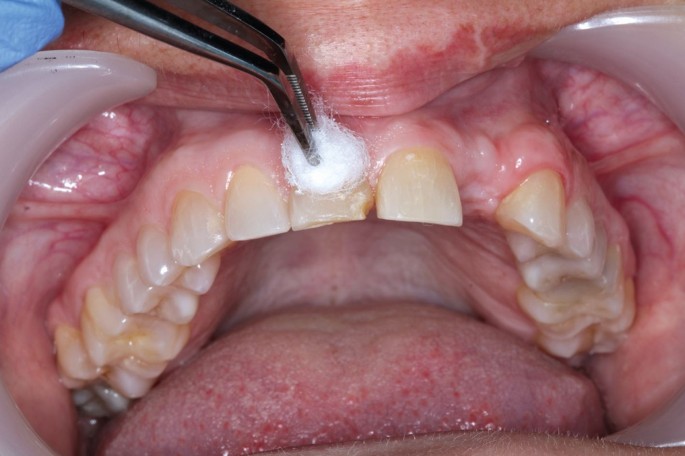

Es un procedimiento en el que se abre la cámara pulpar del diente para eliminar el tejido pulpar infectado o inflamado. Esto ayuda a aliviar el dolor y preparar el diente para un tratamiento de conducto.

Trepanación Pulpar (urgencia)